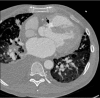

Lactobacillus acidophilus rarely causes bacterial endocarditis, because it usually resides in the mucosa of the vagina, gastrointestinal tract, and oropharynx. Moreover, sinus of Valsalva aneurysms are rare cardiac anomalies, either acquired or congenital. We present the case of a middle-aged man whose bacterial endocarditis, caused by Lactobacillus acidophilus, led to an aneurysmal rupture of the sinus of Valsalva into the right ventricular outflow tract. The patient underwent successful surgical repair, despite numerous complications and sequelae.